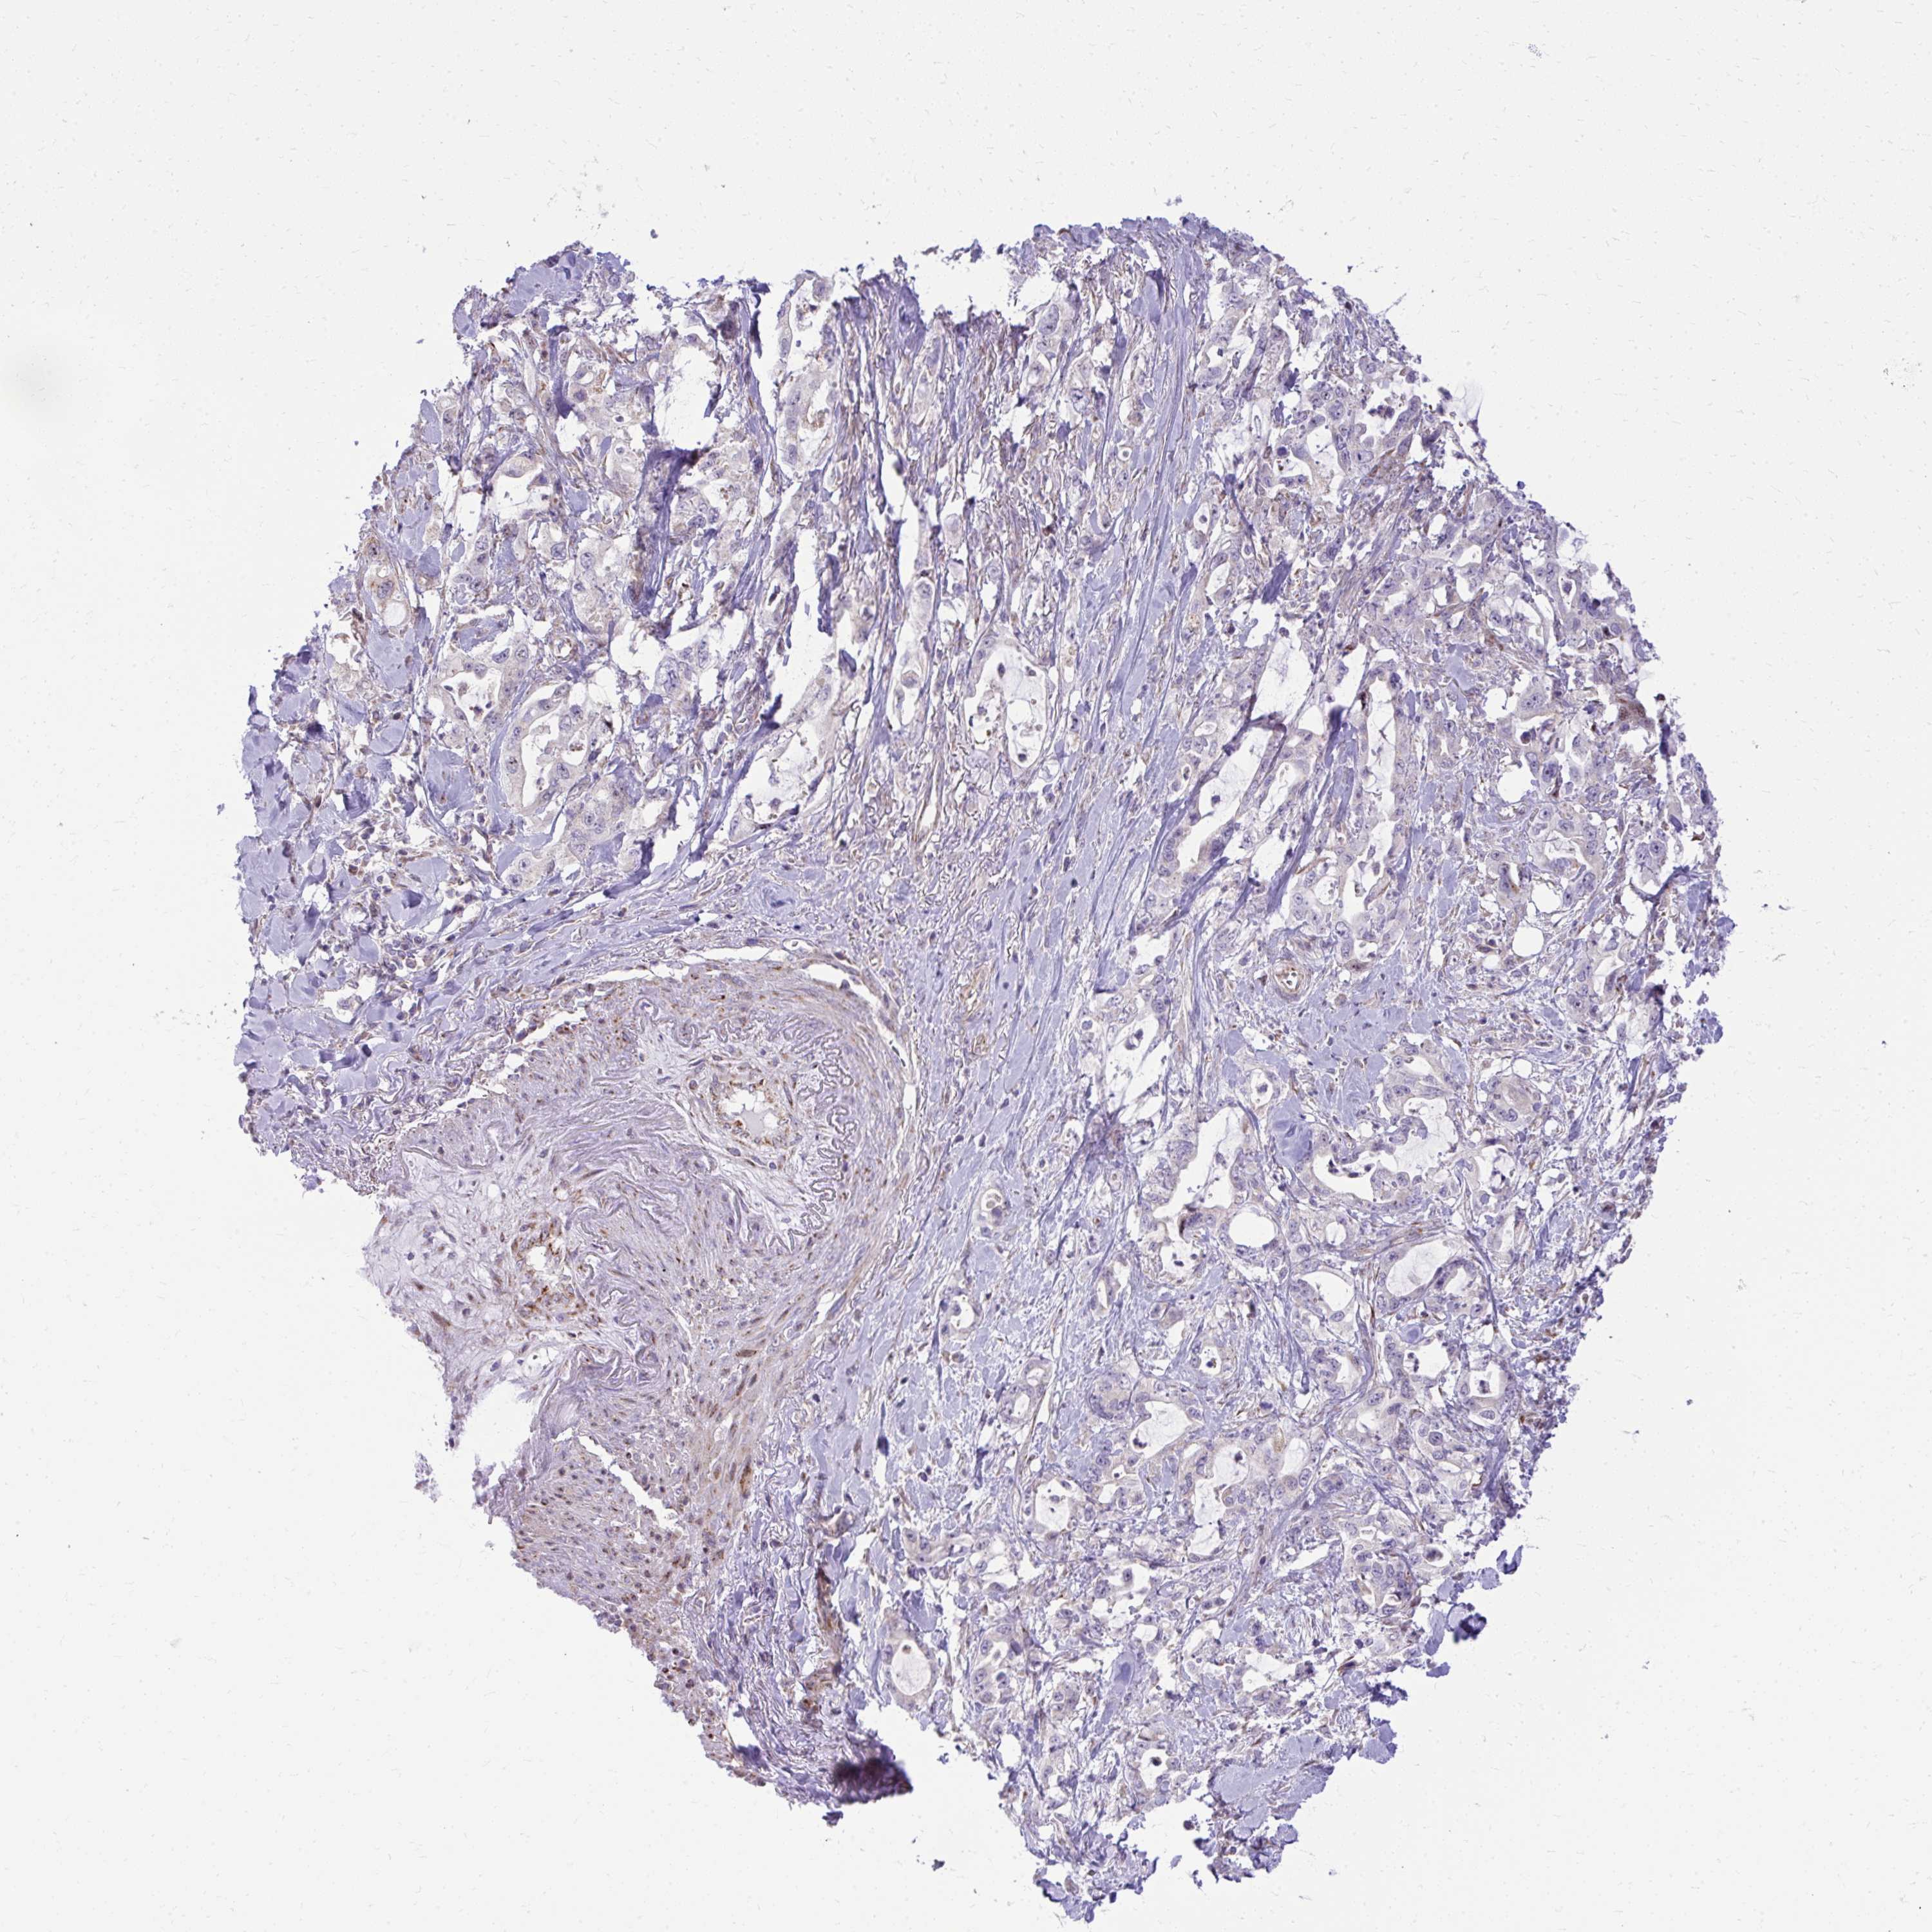

PANCREATIC CANCER - Protein expressioni

A mouse-over function shows sample information and annotation data. Click on an image to view it in a full screen mode. Samples can be filtered based on level of antibody staining by selecting one or several of the following categories: high, medium, low and not detected. The assay and annotation is described here.

Note that samples used for immunohistochemistry by the Human Protein Atlas do not correspond to samples in the TCGA dataset.

Antibody stainingi

Antibody staining in the annotated cell types in the current human tissue is reported as not detected, low, medium, or high, based on conventional immunohistochemistry profiling in selected tissues. This score is based on the combination of the staining intensity and fraction of stained cells.

Each image is clickable and will lead to virtual microscopy that enables deeper exploration of all samples and also displays staining intensity scores, fraction scores and subcellular localization as well as patient and tissue information for each sample.

Antibody HPA057666

Antibody HPA059092

Adenocarcinoma, NOS